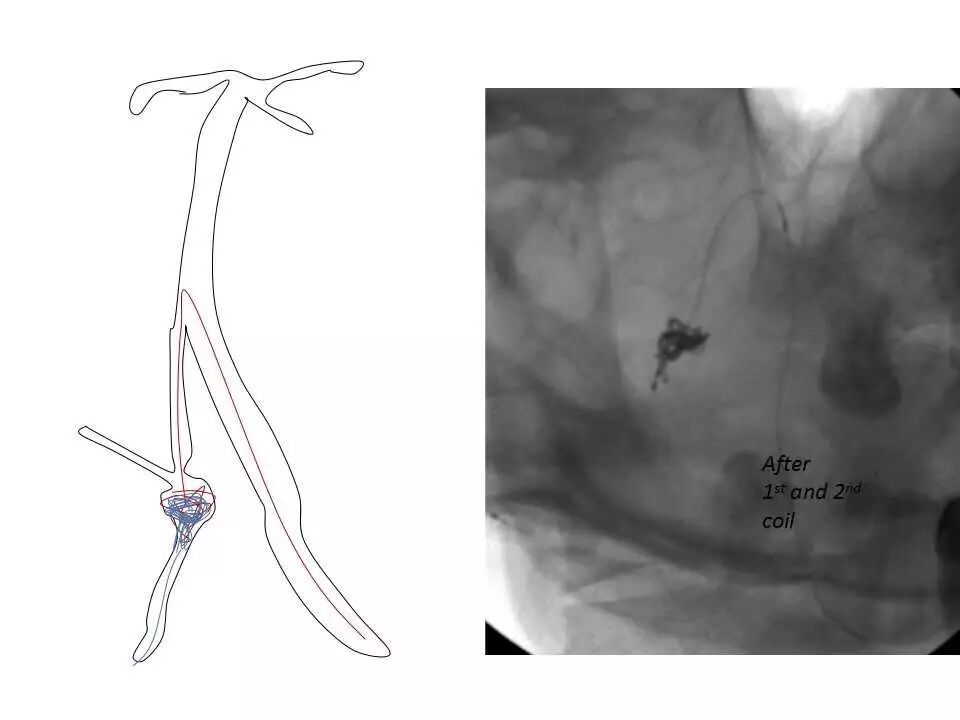

今天为大家分享的是“强生医疗CNV-神经介入专栏”第十五期,由首都医科大学宣武医院何川教授带来的“颅内动脉瘤介入治疗”精彩讲课视频及PPT,欢迎观看、阅读。文章仅代表作者个人观点,如有不同见解,欢迎同道斧正!

何川 ,首都医科大学宣武医院副主任医师,中国医师协会神经介入专业委员会常务委员,长期从事脑血管病和脊髓血管病的手术及介入治疗和相关研究工作。首都医科大学神经外科博士,师从于中国神经介入开创人凌锋教授;日本东北大学医院脑血管病治疗科博士后,师从于日本国脑血管病血管内治疗的开创者高桥教授。